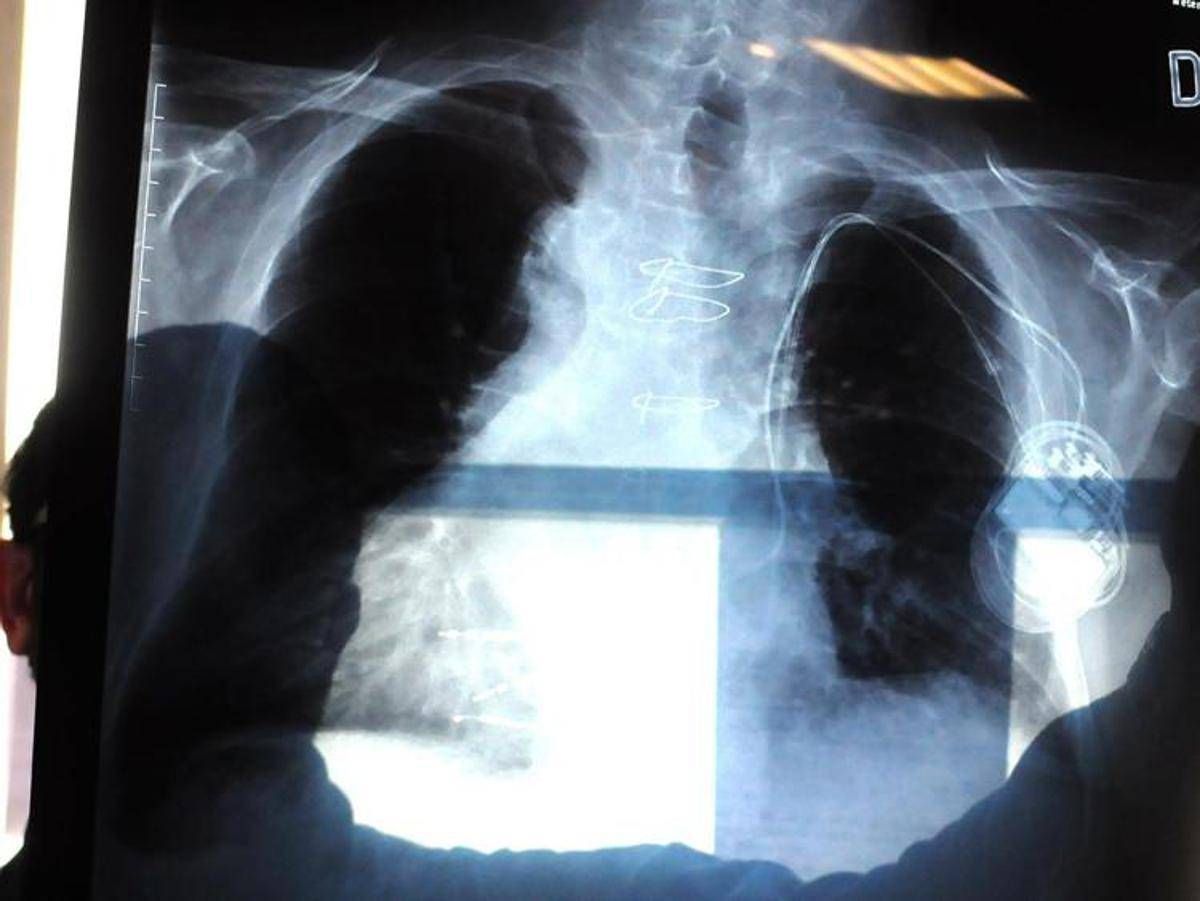

La polmonite, prosegue il presidente di Aipo, è un’infezione che “può essere localizzata in un punto particolare del polmone. L’ente patogeno più frequente in questo caso è lo pneumococco, contro il quale esiste appunto una vaccinazione. Esistono poi le polmoniti interstiziali che colpiscono il tessuto connettivo del polmone, l’area dove avviene lo scambio, per questo l’infezione può essere molto diffusa e anche bilaterale. E’ dovuta prevalentemente a virus, il Covid tra questi, come abbiamo visto durante la pandemia, e ad alcuni batteri. Altro caso abbastanza emblematico è la legionella, oppure i cosiddetti agenti intracellulari, micoplasma e clamidia”. L’intestizio, precisa Micheletto, “è il tessuto di sostegno del polmone, dove avviene il passaggio dell’ossigeno e dell’anidride carbonica nel senso contrario, tra gli alveoli e i capillari. Quando questo interstizio viene colpito, lo scambio viene notevolmente ridotto. Ma se il paziente ha la bronchite cronica o è un fumatore, questi spazi sono già compromessi. E quindi può dare casi gravi”.

Ma quali sono i segnali d’allarme che indicano una possibile polmonite? “Una polmonite si presenta prevalentemente tosse e febbre”, descrive lo pneumologo. Ma la “gravità che causa ospedalizzazione riguarda la difficoltà respiratoria, che può essere altamente rischiosa”, conclude.